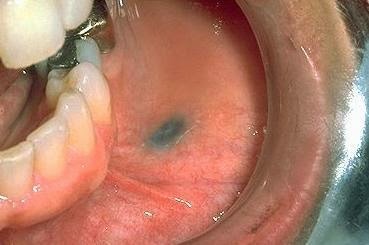

What is this?

Amalgam tattoo (ha! and you thought it was oral melanoacanthoma)